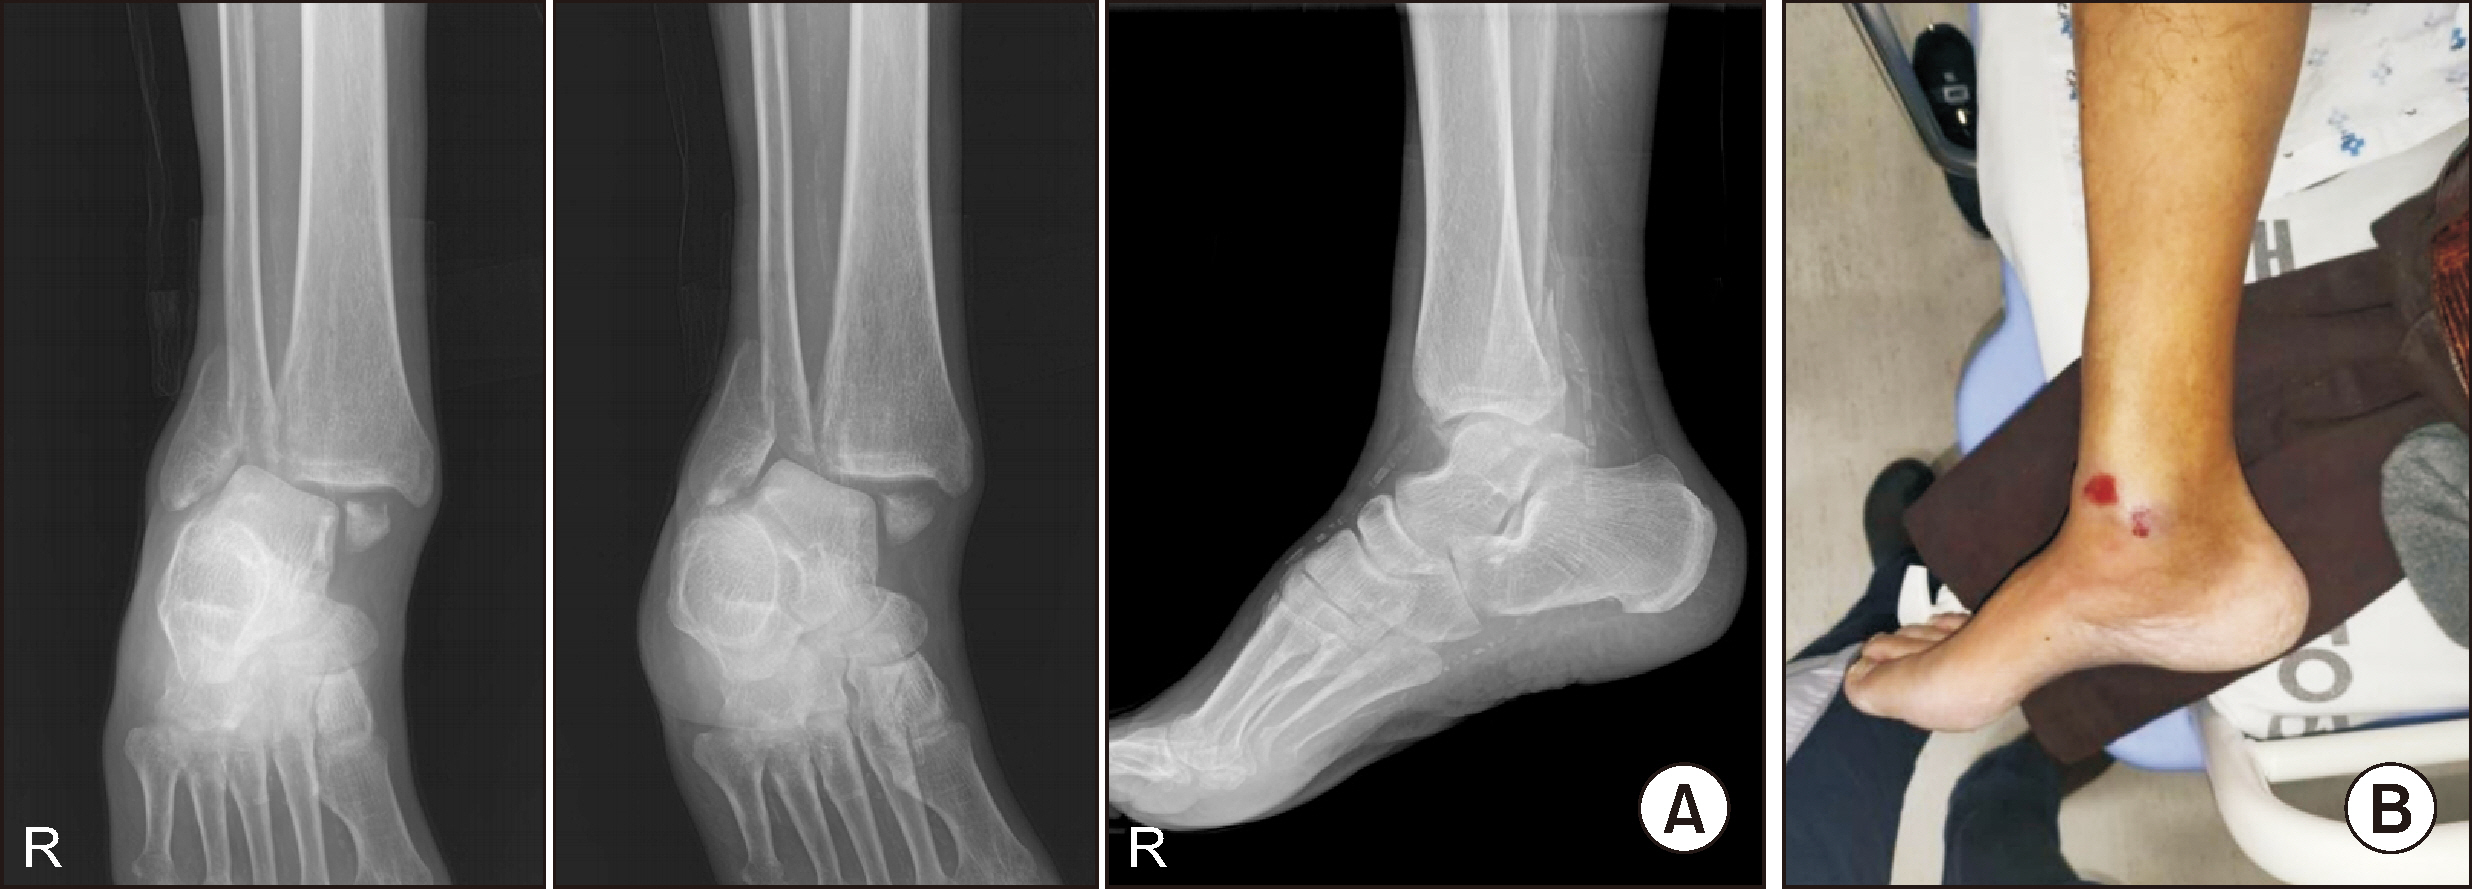

Charcot neuroarthropathy (CN), also known as Charcot arthropathy, is a complex, progressive disorder primarily affecting the foot and ankle. This case report describes a multifaceted management strategy for a 54-year-old male with diabetes mellitus, end-stage renal disease, and presumed underlying Charcot arthropathy who experienced a traumatic ankle fracture. The initial surgical plans were delayed because of systemic infection indicators, including elevated C-reactive protein levels and high fever. The patient underwent multiple surgical interventions and faced challenges, including metal failure, implant-associated infection, and tibiotalar joint dislocation. A multidisciplinary approach involving orthopedic surgeons, nephrologists, and endocrinologists was crucial for managing the case effectively. In particular, the patient declined a below-knee amputation and opted for comprehensive surgical intervention, resulting in improved functionality at the latest follow-up. This case highlights the complexities of managing CN in patients with multiple comorbidities and emphasizes the need for a nuanced, patient-centered approach.